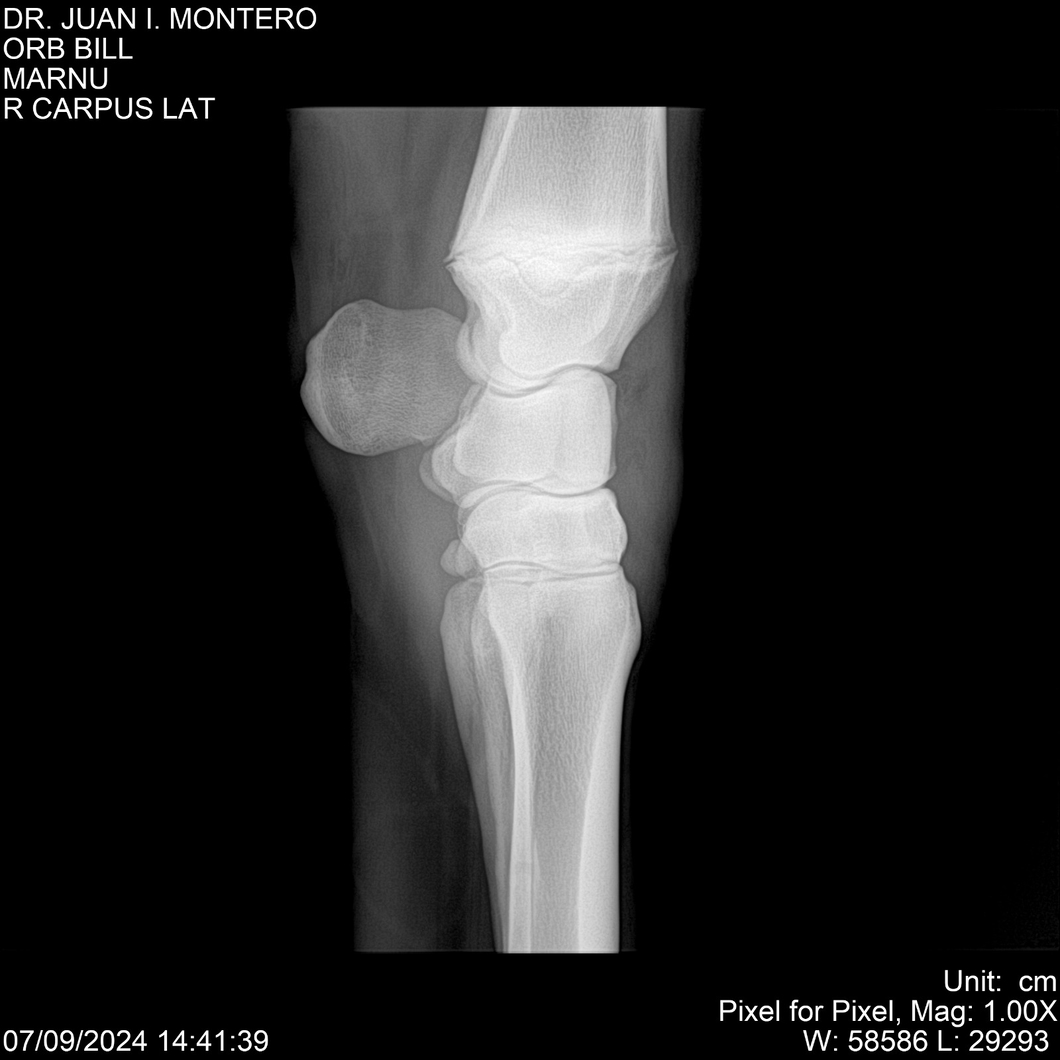

LOTE 7, ORB BILL 🔥 🔥 🔥 Lote Anterior Volver al remate Lote Siguiente Ficha Contacto Montevideo - Ficha del Lote Identificador: #282523 Categoría: Yeguarizos Montevideo - 83 Visualizaciones ClicData Contacto Empresa: Abelenda N. R., Walter Hugo Nombre*: Teléfono* : E-mail* : Mensaje Enviar Registrese gratis Este contenido Exclusivo está disponible sólo para usuarios registrados Ingresar